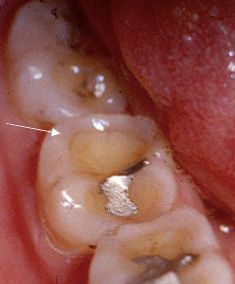

enamel can be white, yellow, brown, and or have different degrees of hypoplasia; most commonly in bicuspid because of their relation ship with the deciduous molars; causes fever, PA inflammatory disease of overlying deciduous tooth, trauma

turner’s hypoplasia

discolored enamel defect - turner’s hypoplasia